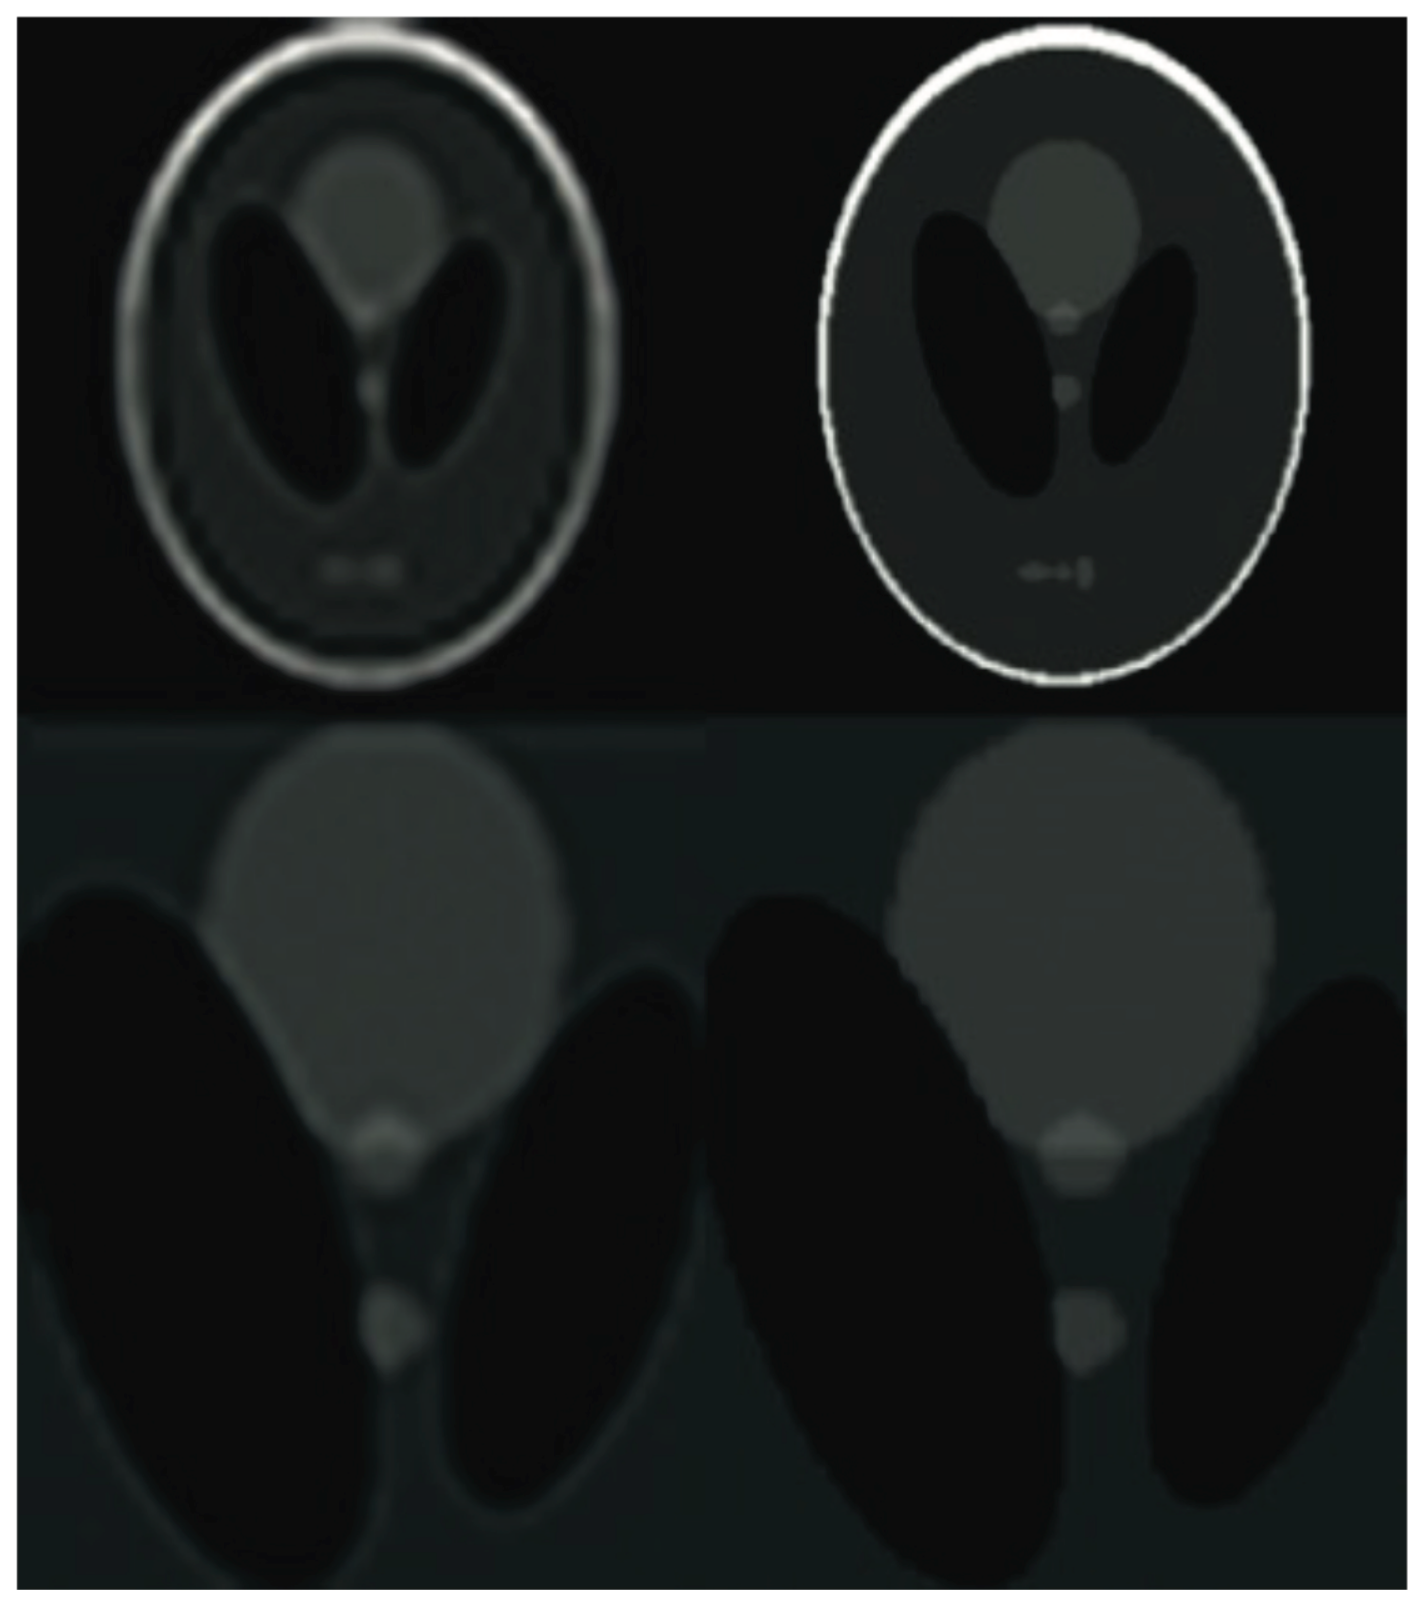

Figure 5. The phantom images based on experiment results. See from the upper row: the unprocessed image corrupted by simulated shift and the reconstructed images with various sampling rates (varying from 25% to 40% and 60% of samples of the ground truth).

In order to measure the performance of the proposed algorithm, both laboratory phantom studies and an in-vivo assessment were performed. The purpose of the experiment was to compare the effectiveness of various ways of obtaining a compressively-sensed input. In a study of the effects of various compressed-sensing ratio on test performance, the test performance of the proposed Super-Resolution Image Reconstruction method was tested. Moreover, several MRI k-space sampling patterns have been compared. Figure 5, Figure 6, Figure 7, Figure 8, Figure 9, Figure 10, Figure 11, Figure 12, Figure 13, Figure 14, Figure 15, Figure 16, Figure 17, Figure 18, Figure 19, Figure 20, Figure 21 and Figure 22 show the achieved results. It must be emphasised that combining Compressed Sensing with Hermitian symmetry property, as well as Partial Fourier allows the shortening of k-space filling when compared to the different k-space sampling schemes, see Figure 1.